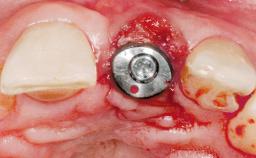

Late Placement of an Implant in a Maxillary Left Central Incisor Site

A 30-year-old female patient had lost tooth 21 and was referred to our clinic for consultation and treatment. Due to advanced apical infection, tooth 21 had been extracted two months earlier at another clinic and an acrylic-resin tooth had been bonded to the adjacent teeth. The patient desired implant treatment to avoid any damage to the adjacent natural teeth. While the patient had no history of any systemic disorder, she was a heavy smoker and exhibited medium to advanced periodontitis in the entire jaw. After the initial treatment to achieve a pocket probing depth of less than 4 mm and no bleeding on probing, a decrease in the height of the papillae mesial and distal to the extraction site and overall gingival recession were observed.

Type of Implants One-Piece|Reduced-Diameter

Attachment One-Piece|Reduced-Diameter